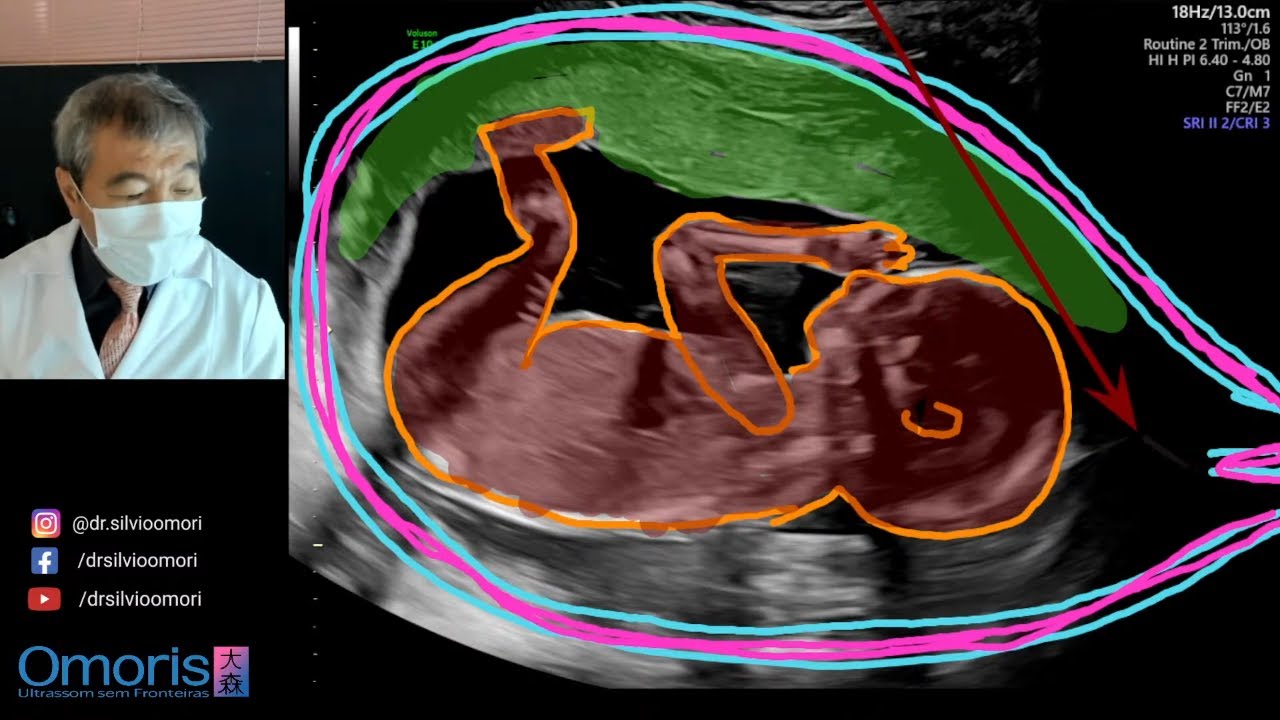

Nuovo Menino ou menina Gravidez 17 semanas.